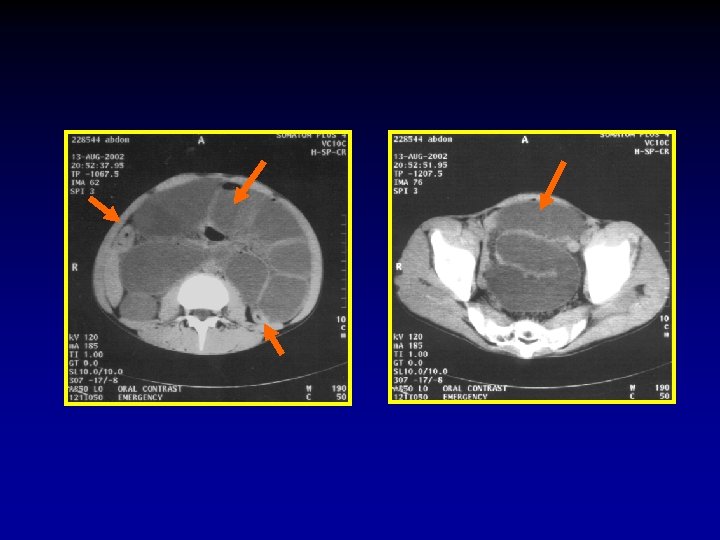

3. What is the level of obstruction? In order to detect the exact level, systematic evaluation should begin at the rectum and proceed towards the caecum. Once the colon is cleared one should attempt to identify the distal ileal loops then proceed up. A common error is to assume that loops in more caudal images are ileal loops and jejunal loops in the proximal images, in fact when the bowel loops dilate they align themselves along the axis of the mesentery thus jejunal loops may appear in the pelvis and ileal loops in the upper abdomen. In small bowel obstruction the transverse colon will not be seen because it is compressed against the anterior abdominal wall by the tensely distended small bowel loops.